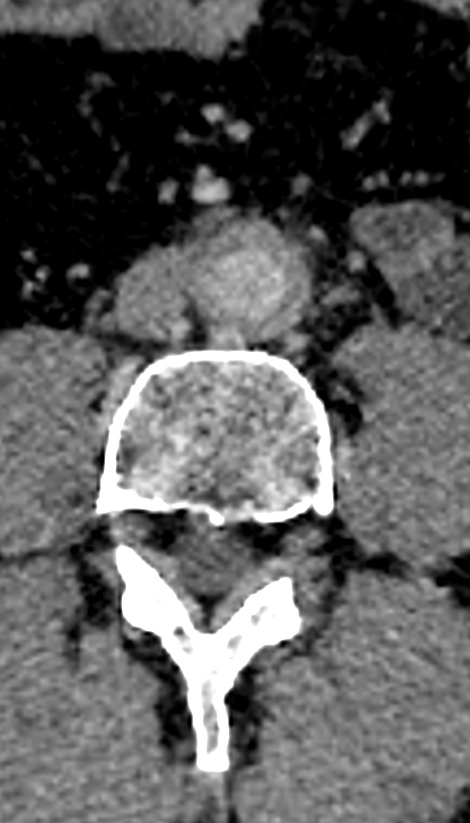

A aortite é a inflamação da parede da aorta, podendo se estender para ramos como as artérias ilíacas comuns. Essa condição pode causar espessamento vascular e alterações no fluxo sanguíneo, muitas vezes detectadas por exames de imagem.

Baseia-se na correlação clínica e laboratorial associada à imagem vascular. A angio-TC contrastada é um dos principais métodos de avaliação, sendo referência prática na investigação e acompanhamento.

Imagem 1